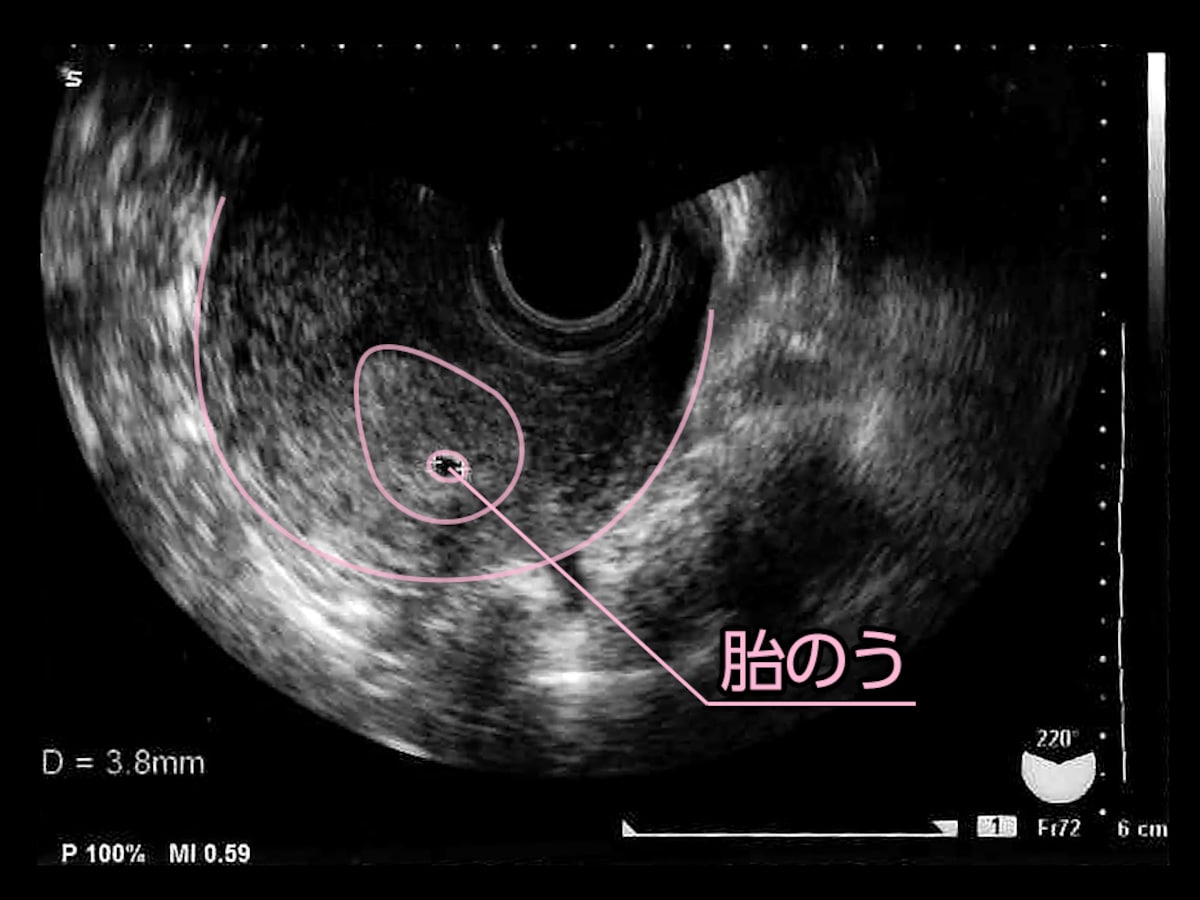

胎嚢の大きさの平均ってどれくらいなの ママリ

妊娠5週目 胎嚢のエコー写真 つわり症状や流産のこと 妊娠初期 All About

妊娠4週 3 6日 のエコー写真 体験談

妊娠4週目ですが胎嚢が小さいので 成長が止まっちゃってるか子宮外妊娠 妊娠 教えて Goo

妊娠4週3日 4w3d の超音波 エコー 写真

妊娠4週4日 4w4d の超音波 エコー 写真

妊娠4週 赤ちゃんのエコー写真 超音波写真まとめ たまひよ